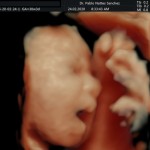

Los objetivos más importantes de esta ecografía son la evaluación de:

- La vitalidad y el bienestar fetal (Doppler).

- Crecimiento fetal.

- Las estructuras anatómicas fetales: diagnóstico de Malformaciones Estructurales de aparición tardía (displasias esqueléticas, alteraciones cardiacas pequeñas, alteraciones la vía urinaria y obstrucciones intestinales.

- Rastreo de alteraciones cromosómicas (sensibilidad del 55% aprox.).

- El escenario Gravídico: Placenta, liquido y Anexos.

- El Doppler de las arterias uterinas maternas y determinación de riesgo para pre eclampsia severa.